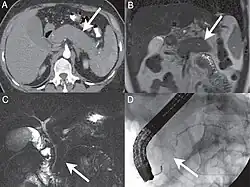

| A. Axial CT image in the pancreatic parenchymal phase shows the typical enlarged, poorly enhancing gland. B. Coronal T2 Weighted MR image demonstrates low signal intensity in the pancreas due to the diffuse fibrosis in the gland. C. Coronal MRCP image depicts a diffusely irregular pancreatic duct with stenosis distally in the pancreatic head. D. ERCP confirms the MR findings including the ductal stenosis. | |

Computed tomography (CT) findings in AIP include a diffusely enlarged hypodense pancreas or a focal mass that may be mistaken for a pancreatic malignancy.[8] A low-density, capsule-like rim on CT (possibly corresponding to an inflammatory process involving peripancreatic tissues) is thought to be an additional characteristic feature (thus the mnemonic: sausage-shaped). Magnetic resonance imaging (MRI) reveals a diffusely decreased signal intensity and delayed enhancement on dynamic scanning. The characteristic ERCP finding is segmental or diffuse irregular narrowing of the main pancreatic duct, usually accompanied by an extrinsic-appearing stricture of the distal bile duct. Changes in the extrapancreatic bile duct similar to those of primary sclerosing cholangitis (PSC) have been reported.